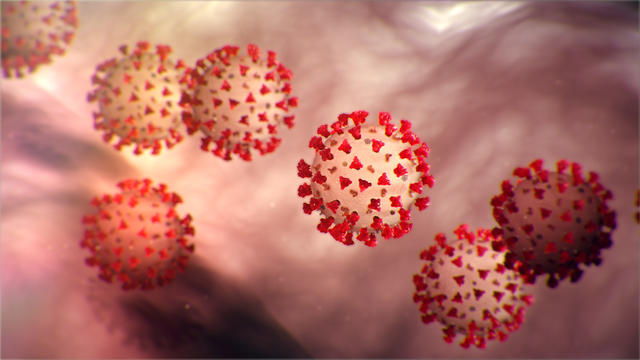

The Centers for Disease Control and Prevention said Tuesday that it expects the coronavirus will spread in the U.S. and asked citizens to prepare.

A person in northern Virginia is being tested for the coronavirus, the state's health department reported Wednesday.

The Centers for Disease Control and Prevention announced Tuesday it expects the coronavirus will spread in the U.S. and asked citizens to prepare.

Coca-Cola says coronavirus has disrupted its supply chain, and artificial sweeteners from China could be in shorter supply if the outbreak continues to spread.